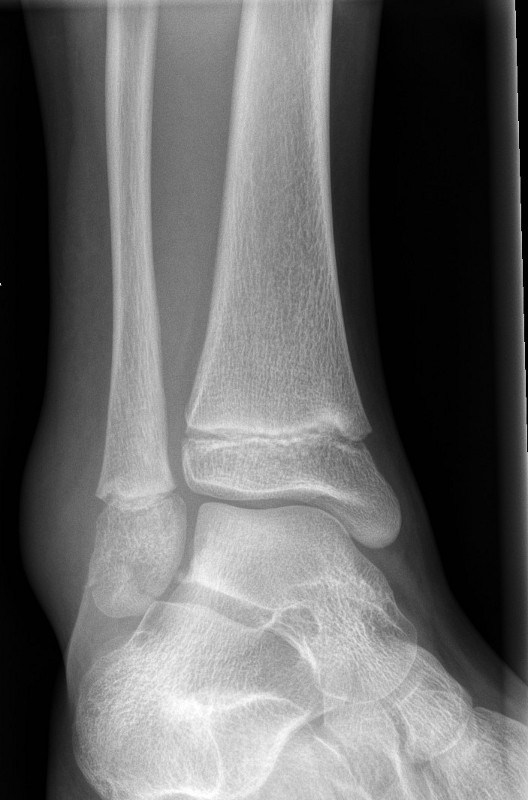

Minimally displaced Salter-Harris II fracture of the distal tibia

Salter-Harris II fractures of the distal tibia

- Often occur in combination with a greenstick fracture of the fibula.

- If undisplaced, manage in a below knee plaster backslab non weight bearing with crutches with follow up in Orthopaedic Fracture clinic in 7-10 days.

- If displaced, refer to the Orthopaedic Team.